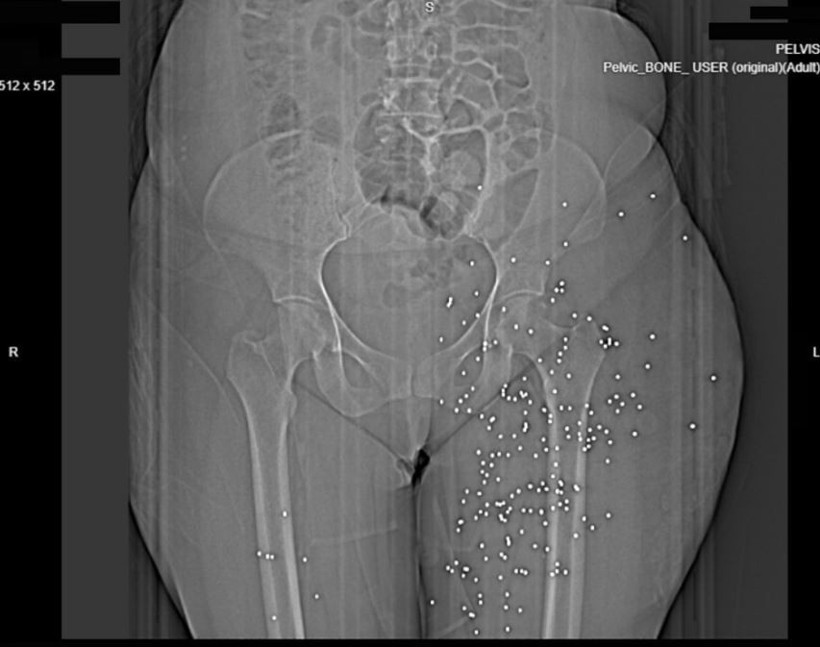

İngiliz gazetesi The Guardian ve söz konusu bilgilerin doğruluğunu teyit eden Factnameh'nin gerçekleştirdiği ortak araştırmada, ülkenin büyük şehirlerinden birinde yer alan bir hastaneden elde edilen 75'ten fazla röntgen ve bilgisayarlı tomografi görüntüsü yayınlandı.

Bu görüntüler, güvenlik güçlerinin yüksek kalibreli silahlar ve birdshot mühimmatı kullandığına dair iddiaları destekliyor. Röntgenlerin büyük bölümünde, protestoculara karşı “birdshot” olarak adlandırılan mermilerin kullanıldığı belirtiliyor.

Uzmanlar, bu tür mühimmatların uzak mesafelerde geniş bir alana yayıldığını, ancak yakın mesafeden atıldığında ciddi ve hayati tehlike içeren yaralanmalara yol açabileceğini ifade etti.

Saldırıların çoğunlukla yüz, göğüs ve genital bölgelerde yoğunlaştığı da dikkatlerden kaçmadı. 2022 yılında başlayan “Kadın, Yaşam, Özgürlük” protestolarında da benzer yaralanma örüntüleri gözlenmişti.

Guardian'a konuşan İranlı doktorlar, protestocuların özellikle göz, göğüs ve genital bölgelerinin hedef alındığını ifade etti. Bazı sağlık çalışanları, pek çok hastada görme kaybı meydana geldiğini ve bunu yaşayanlar arasında çocukların da bulunduğunu belirtti.

Uzmanlar, genital bölgeyi hedef alan saldırıların uzun vadede ciddi sonuçlar doğurabileceğini, kalıcı kısırlık riskinin yüksek olduğunu vurguladı.